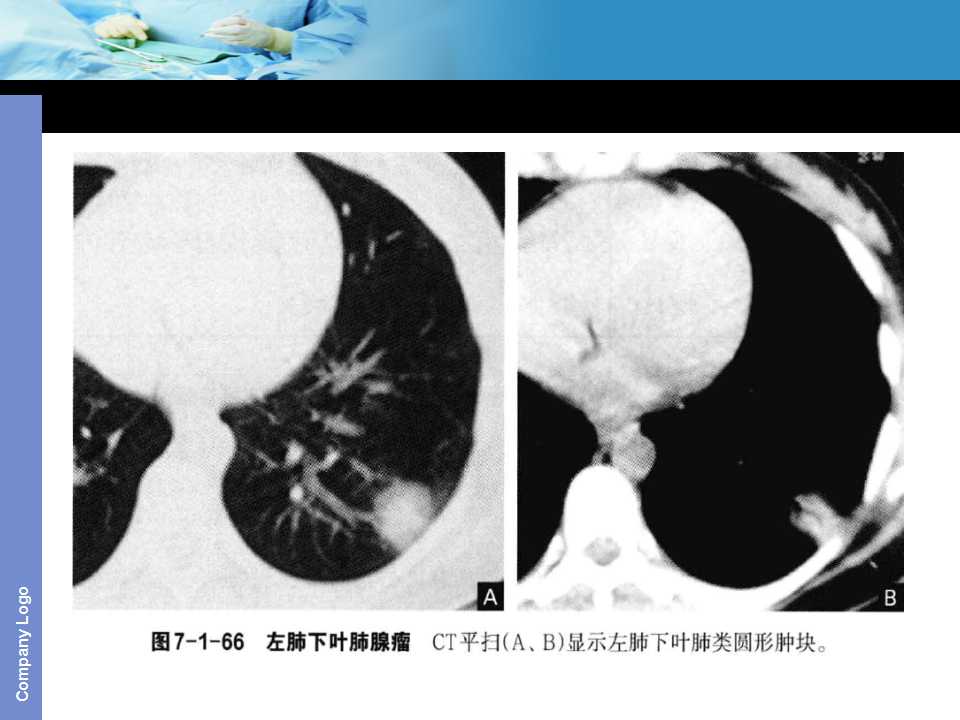

肺癌影像诊断